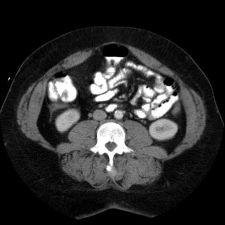

This is an image from a contrast enhanced abdominal CT.

These are images from a contrast enhanced abdominal CT.

Fluid in the right paracolic gutter, and a thickened, inflamed appendix with thickening of the adjacent cecal wall.

Differential: Acute appendicitis is by far the most likely diagnosis.

No appendicolith is seen in this case.

The appendix is normally less than 7 mm in diameter, or if fluid filled, the wall can be up to 3mm thick. This appendix is distended, and the adjacent stranding and fluid indicates the inflammatory process which is causing peritoneal irritation and pain. Here is a series of images showing a normal appendix using similar technique. Note the thin walls of the normal appendix.